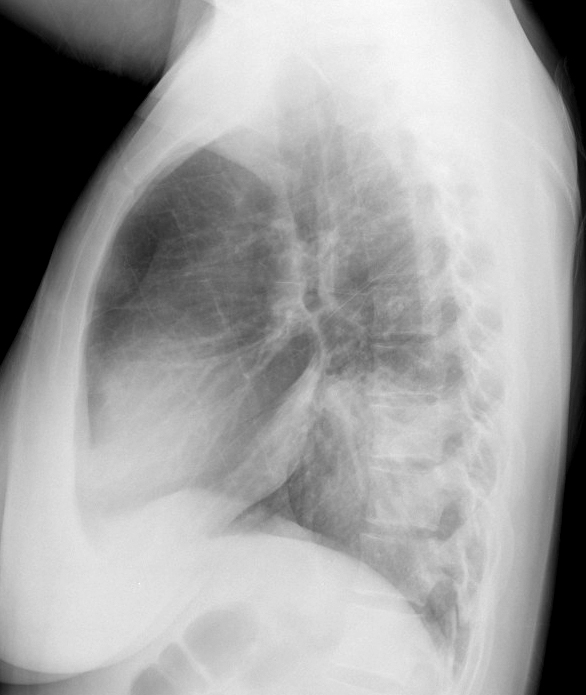

Gallery Pneumonia Case 14 RLL pneum Lat

Case 14 RLL pneum Lat